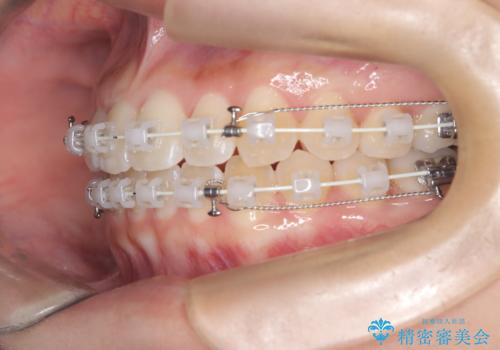

治療では、審美ワイヤーを使用し、目立ちにくく配慮しながら矯正を進めました。上顎にリンガルアーチと矯正用アンカースクリューを用いて臼歯部を安定的に遠心移動させ、歯列全体のスペースを確保しました。その後、回転していた前歯を正しい位置に配列し、全体的な歯並びの改善を行いました。治療中は、装置の適切な管理と口腔衛生を徹底することが重要でした。結果として、見た目だけでなく機能的にも優れた歯列を実現することができ、患者様にもご満足いただけました。

- 治療計画